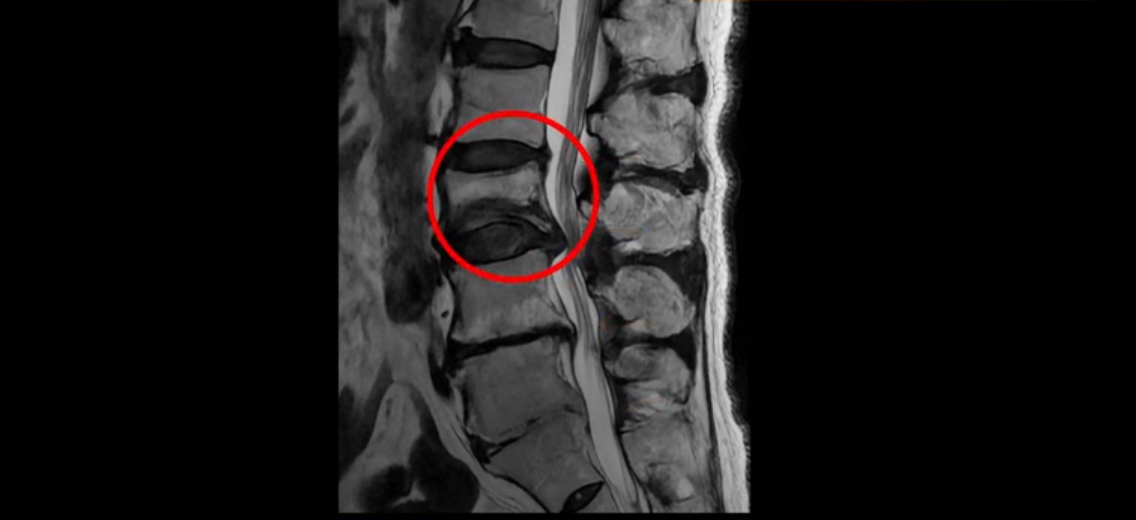

MRI를 보면 허리 4마디가 심하게 퇴행되어 있고

3번 뼈는 넘어질 때 생긴 압박골절이 있습니다.

3번 4번에는 척추관협착과 디스크 탈출이 보이고

4번 5번에는 척추관협착과 심한 디스크 파열이 있습니다.

5번 1번에는 뼈가 자라난 골극이 있고

기립근의 지방화도 심합니다. 또 3번 4번 마디에서는 신경가지가 빠져나가는 추간공이 왼쪽, 오른쪽 모두 많이 좁아져 있습니다.